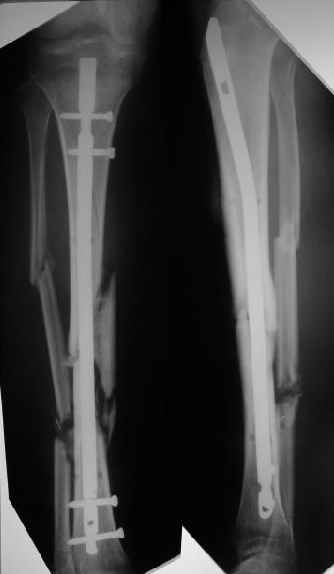

1

Наконец, 23 марта сделали и голень.

Сергей Зырянов 10 Апрель 2004, 19:43

Пациент вернулся. Результаты лечения удовлетворяют его.

Буду продолжать наблюдать, лечить.

Раны зажили хорошо, швы снял. Сделали контрольный рентгеновский снимок бедра. Движения в коленном суставе востанавливаются, угол 94 гр.

Больной ходит пока с костылями, с неполной нагрузкой весом тела, он боится больше нагружать.